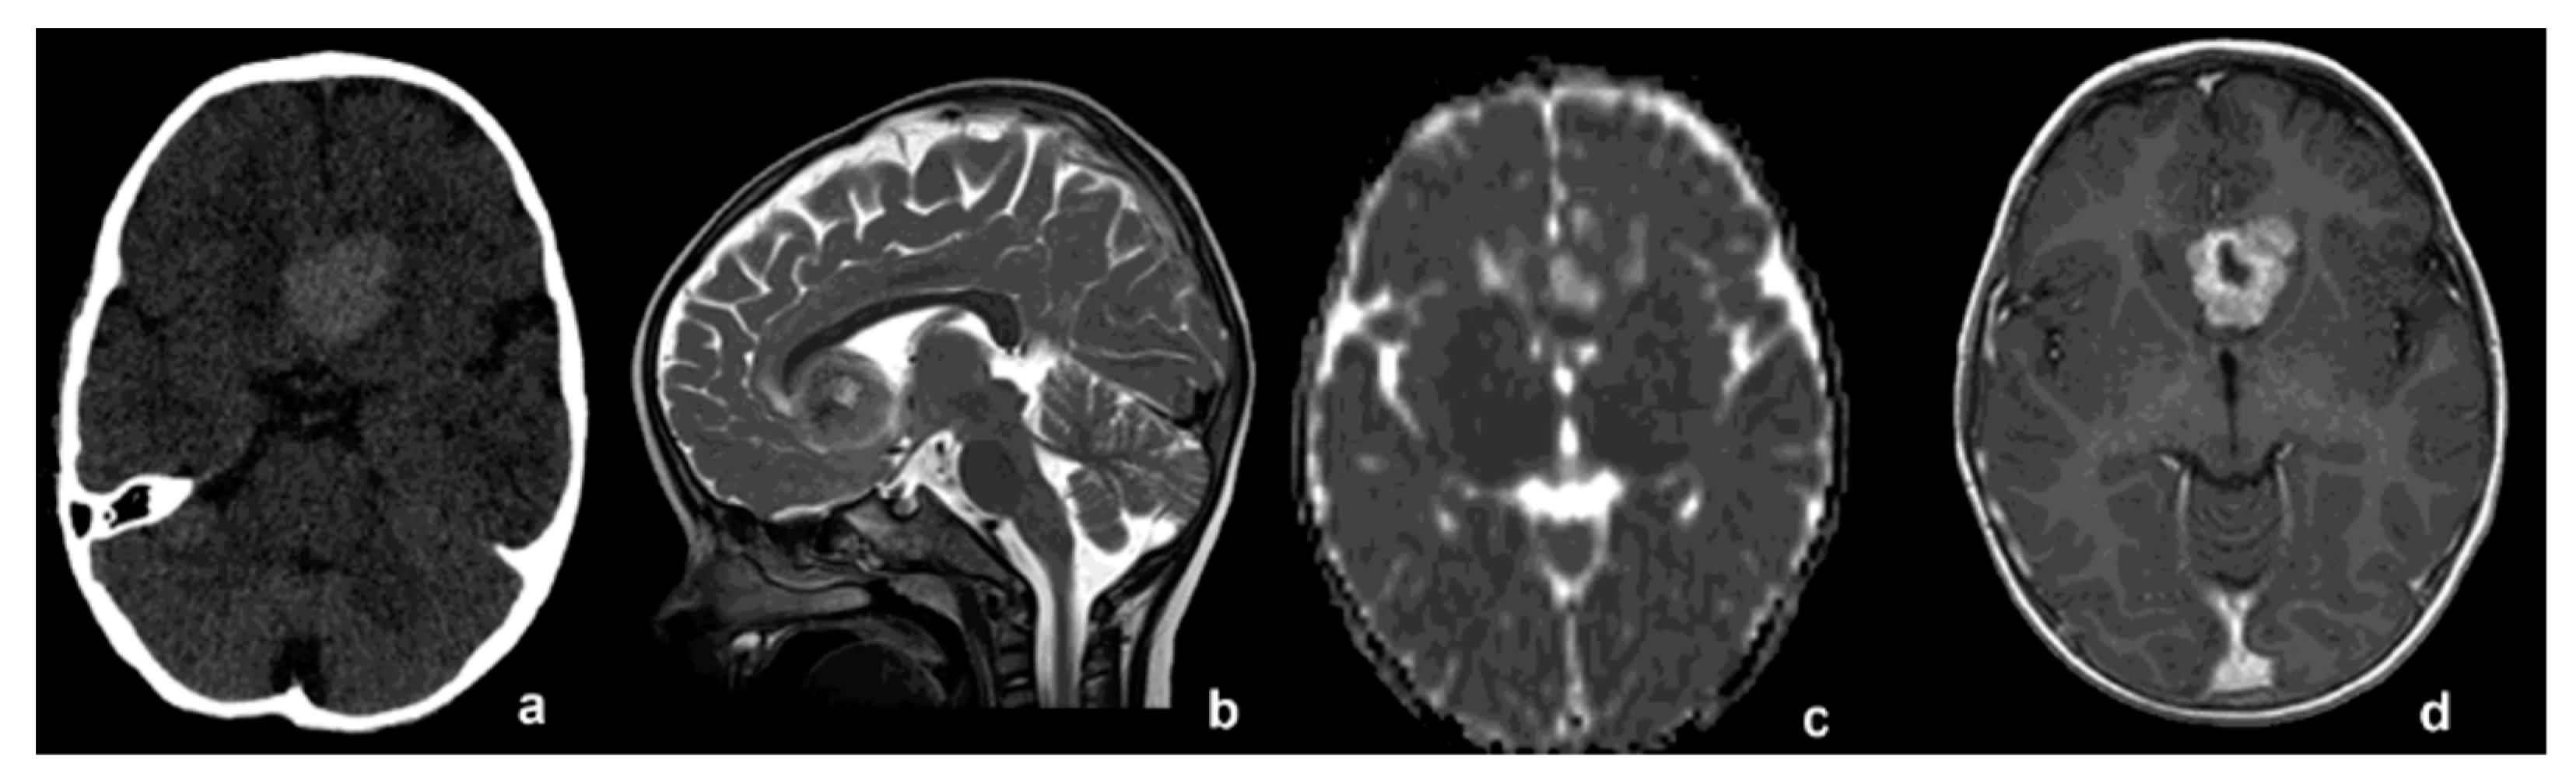

2. Case Report